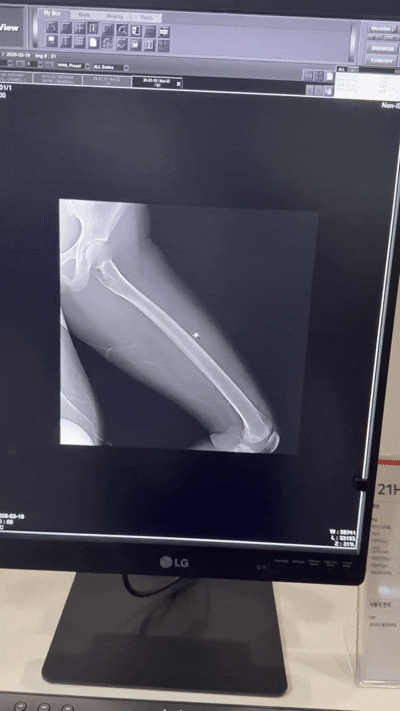

디지털 엑스레이 전시 공간에도 관람객들이 모였다.

이중에너지 촬영 기술 시연이 진행되는 구역에서는 관람객들이 촬영 결과 이미지를 비교하며 관심을 보였다.

연부조직과 뼈 이미지를 분리해 영상 중첩을 줄이고, 미세 병변 식별 정확도를 높이는 기술이 적용됐다.